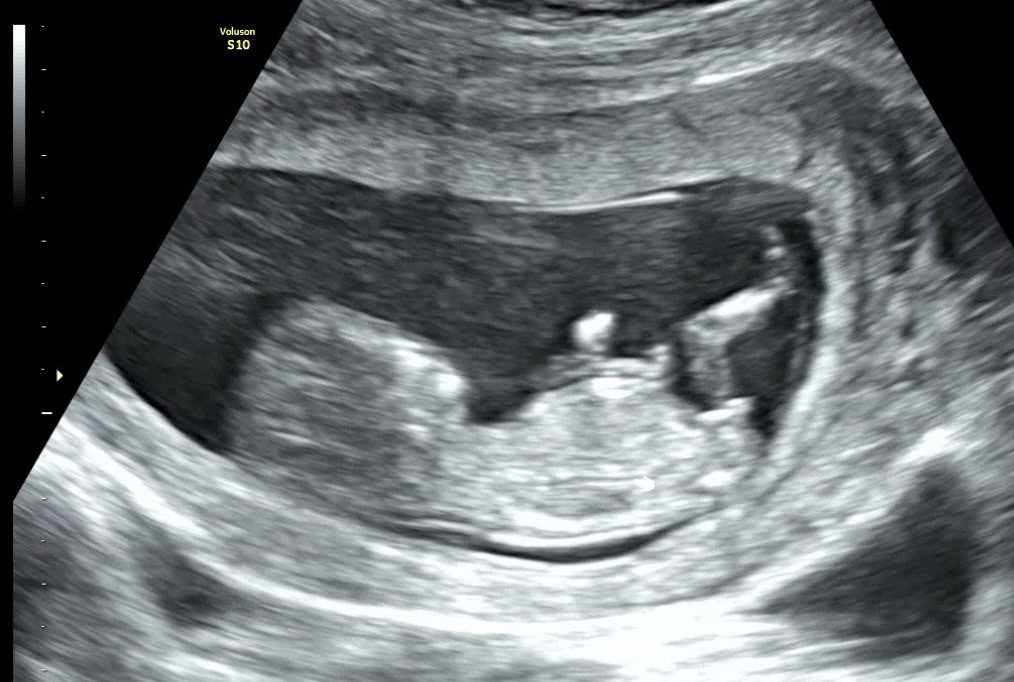

아들&딸 뭘까요?!! 투표해주세용..❤️

아들일까용 딸일까용?